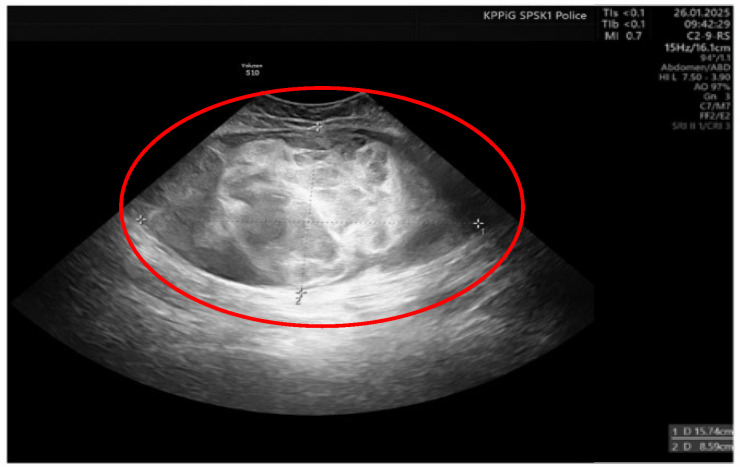

Case presentation: We report the case of a 36-year-old female patient on the 11th day of the puerperium after a cesarean section. The patient presented to the gynecology ward owing to the sudden appearance of a tumor in the medial part of her right thigh. The lesion was non-painful, mobile, soft, approximately 20 cm in diameter, and protruded above the level of the rest of the thigh surface. A suspicion of hematoma was raised. The final diagnosis was high-grade MLPS.